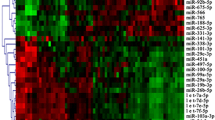

In this study, we first profiled differentially expressed miRNAs in serum samples of health control, PSC, and CCA and found that 30 dysregulated serum miRNAs in PSCs were not observed in healthy control sera (P < 0.01). Of them, 15 were upregulated and 15 were downregulated (Fig. 1a). Moreover, there were 19 dysregulated serum miRNAs in CCAs that were not found in healthy control sera (P < 0.01), of which 5 were upregulated and 14 were downregulated (Fig. 1b). There were 66 dysregulated bile miRNAs in CCAs that were not found in healthy control sera (P < 0.01), of which 36 were upregulated and 30 were downregulated (Fig. 1c). In addition, there were nine miRNAs dysregulated in both CCA sera and bile (Fig. 1d), while three miRNAs were altered in both PSC and CCA compared to the health control, i.e., miR-4484 and miR-3178 (upregulated) and miR-150-5p (downregulated; Fig. 1e). It is therefore speculated that these three miRNAs could play a key role in CCA development and progression. We then further pursued miR-150-5p in this study.

Profiling of differentially expressed miRNAs in CCA sera. Differentially expressed miRNAs were profiled in three cases of each of healthy control (normal), PSC, and CCA with matched bile samples (CCAB) using miRNA microarrays. a Thirty deregulated serum miRNAs in PSCs compared to healthy controls (P < 0.01). b Nineteen deregulated serum miRNAs in CCAs, which were not found in healthy controls (P < 0.01). c Sixty-six deregulated bile miRNAs in CCAs (CCAB) that were not found in sera of healthy controls (P < 0.01). d Nine deregulated miRNAs in CCA sera and bile (P < 0.01). e Three altered miRNAs in both PSC and CCA. The top bar represents the levels of miRNA expression from −1.99 (green) to 1.99 (red). The individual identity of significantly deregulated miRNAs is shown on the right